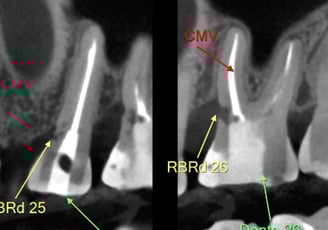

Tratamento endodôntico cirúrgico

Em casos em que a raiz deve ser acessada diretamente, quando há grandes lesões, obstruções da coroa do dente, reabsorções, perfurações....